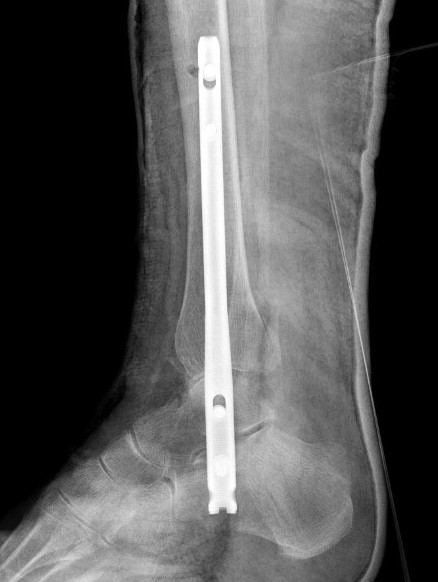

Hindfoot nail

Technique

Insertion point

- in line with 2nd metatarsal / center of heel pad

- junction of posterior 2/3 and anterior 1/3 heel

- should pass through anterior aspect posterior subtalar joint

- posterior to lateral plantar artery and nerve

Screw fixation

- distal screw fixation in calcaneum +/- talus with jig

- compression

- proximal screws medial to lateral